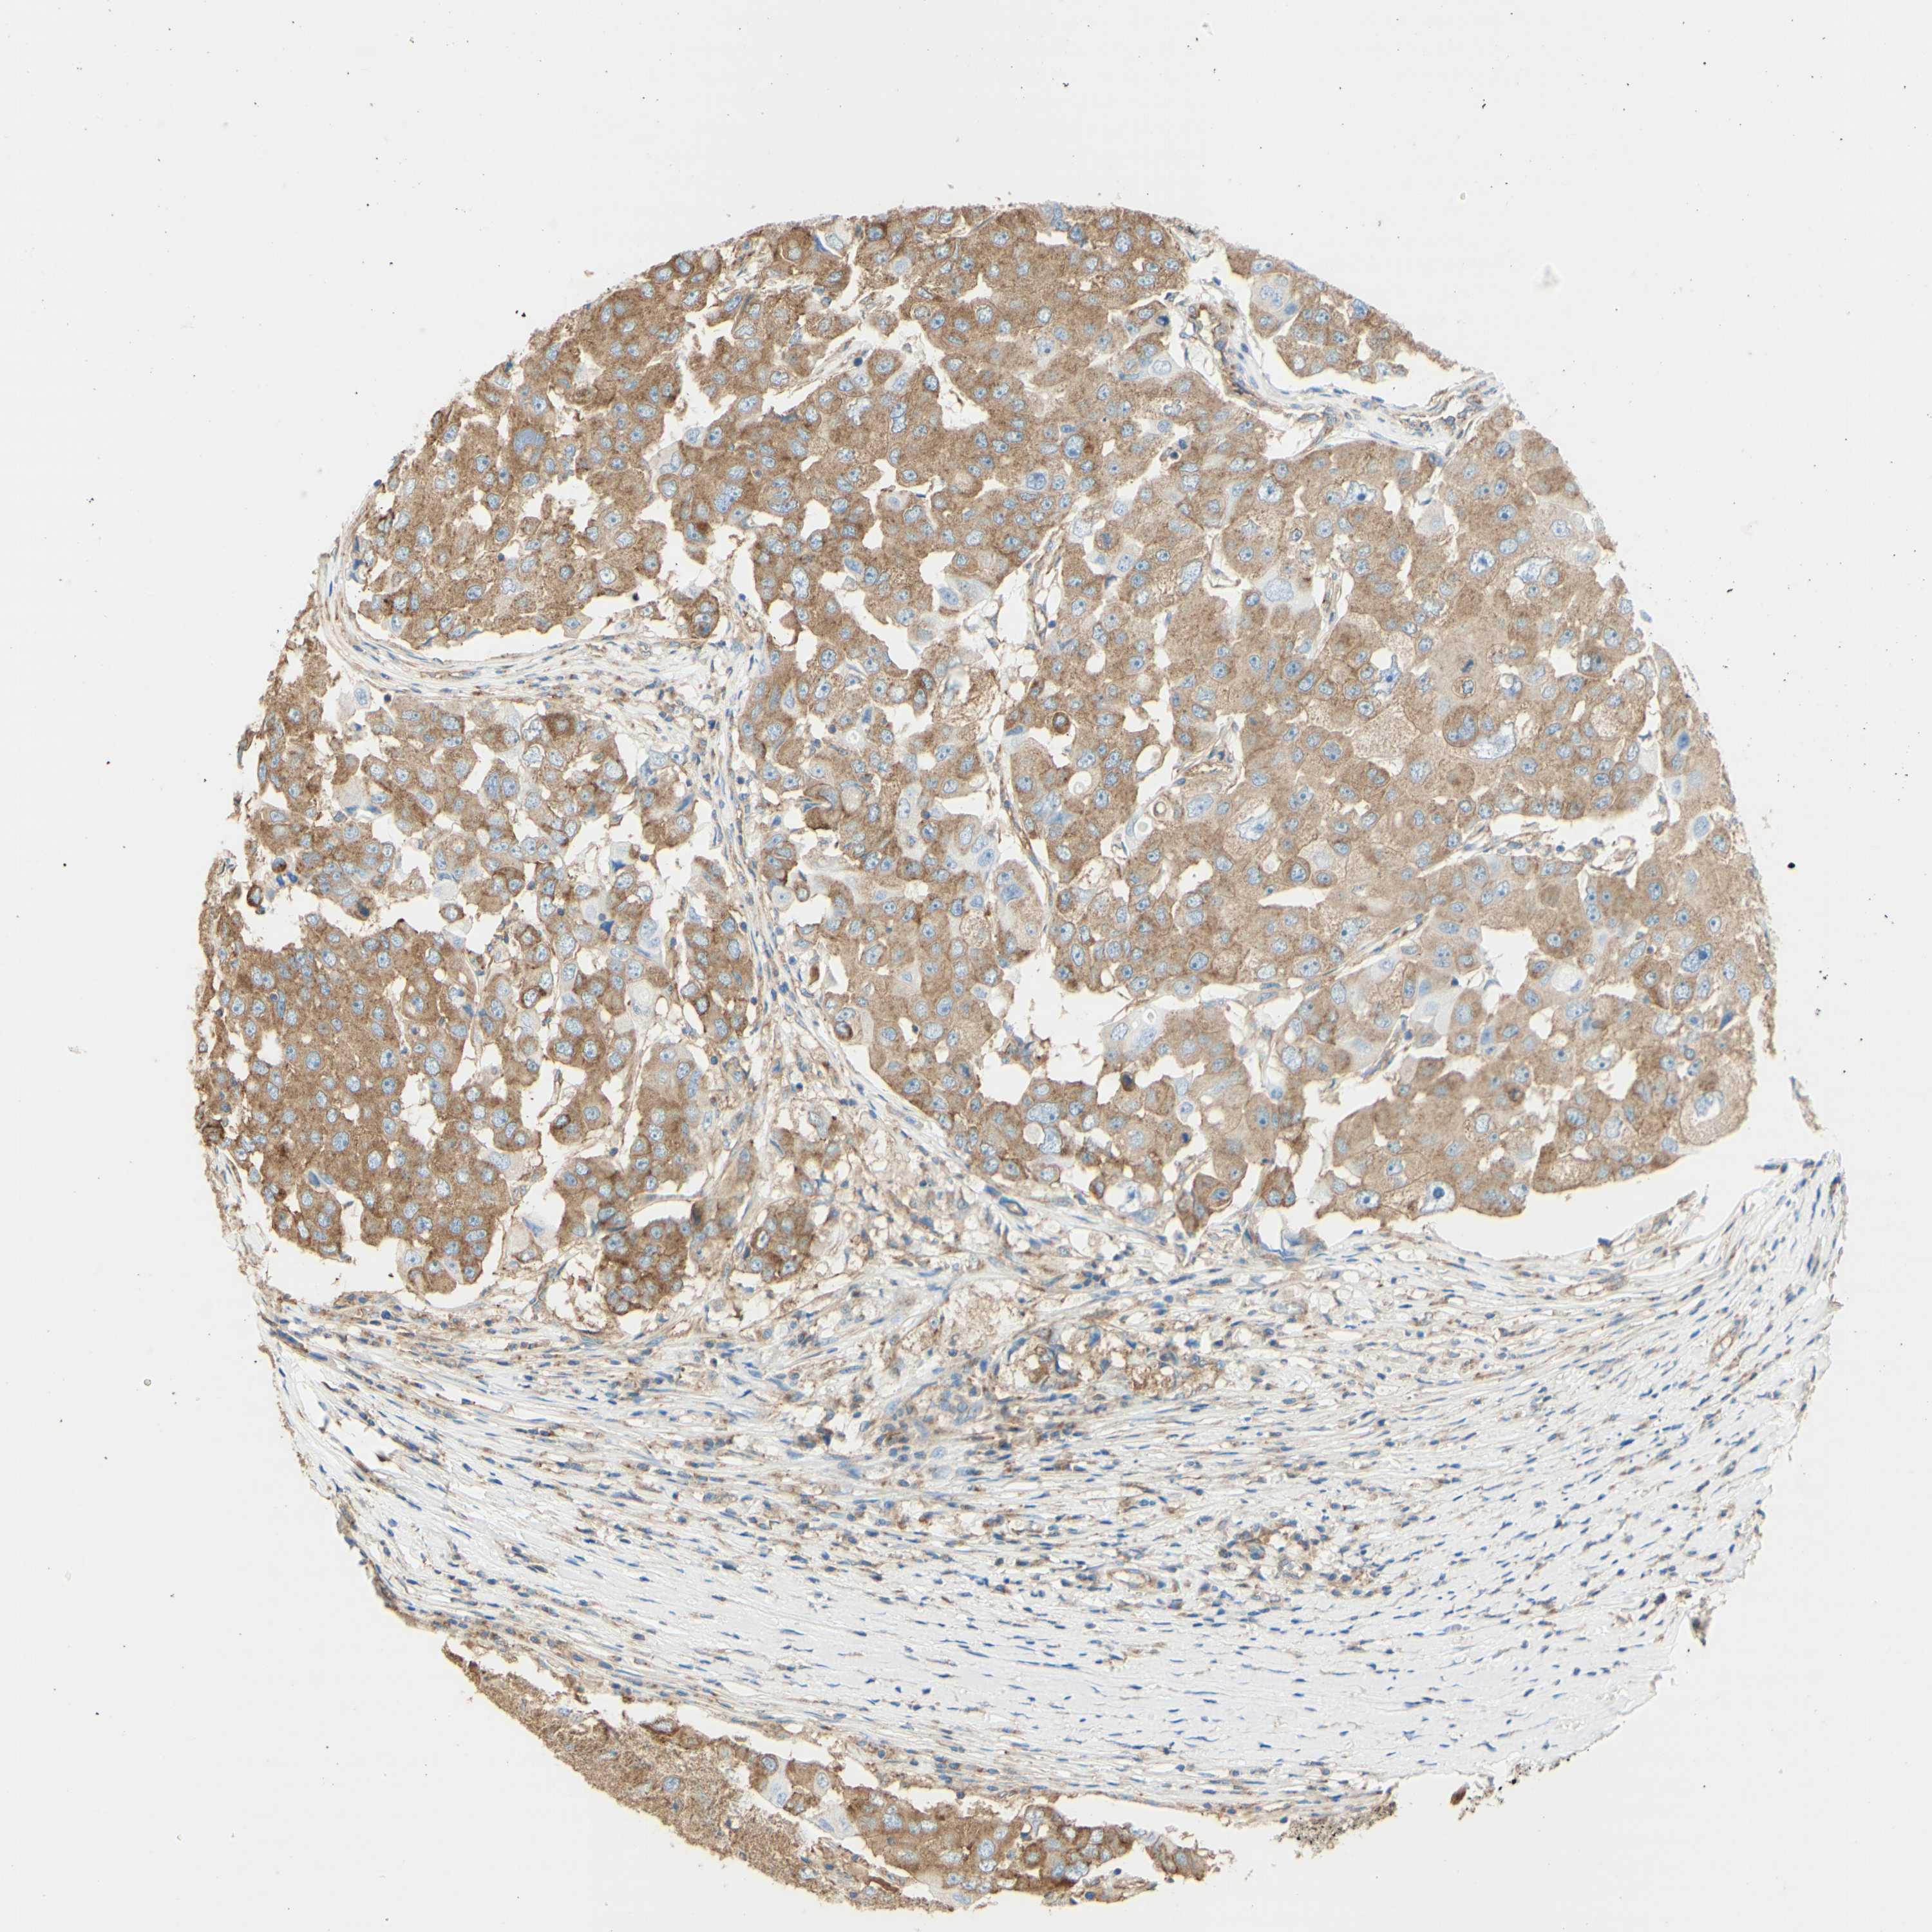

CANCER BREAST CANCER Show tissue menu

BRCA TCGA BRCA VALIDATION PROTEIN EXPRESSION